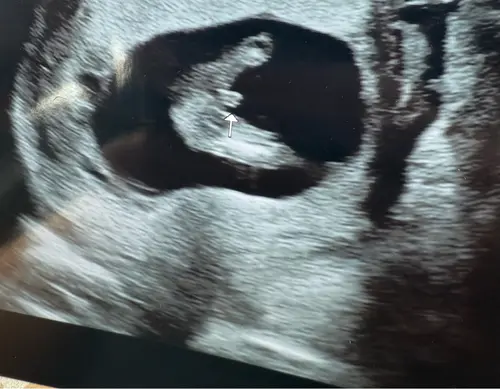

Dit is de potty shot die ik heb, zien wij het echt goed ? Het is nog een beetje moeilijk te bevatten 😆